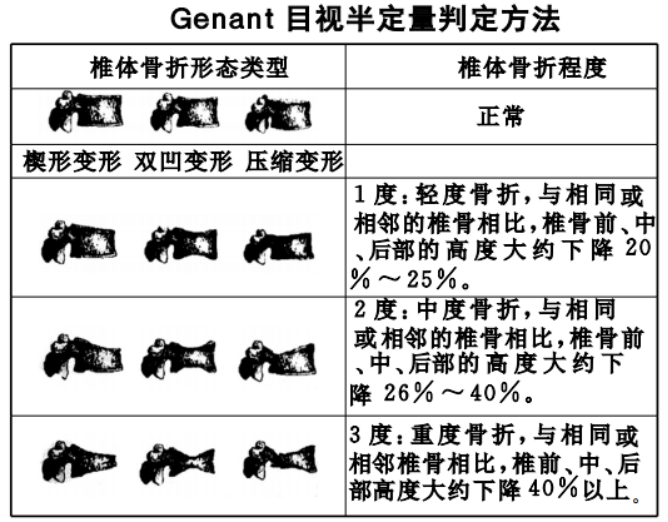

(1)基于椎体形态改变将OVCFs分为3型:椎体压缩呈楔形骨折、双凹骨折和垂直压缩性骨折,

A.椎体楔形骨折:椎体前方高度变小,后方高度不变;

B.双凹状骨折:椎体前方,后方高度不变,中间高度变小;

C.压缩性骨折:椎体各部分高度均变小。其中最常见的是楔形压缩骨折(51%),常导致患者腰背痛、脊柱后凸畸形、呼吸功能降低等一系列并发症。

(2)根据Genant等将X线分型标准OVCFs分为:

A.轻度压缩骨折:在原椎体高度上压缩20%-25%。

B.中度压缩骨折:在原椎体高度上压缩25%-40%。

C.重度压缩骨折:在原椎体高度上压缩>40%。